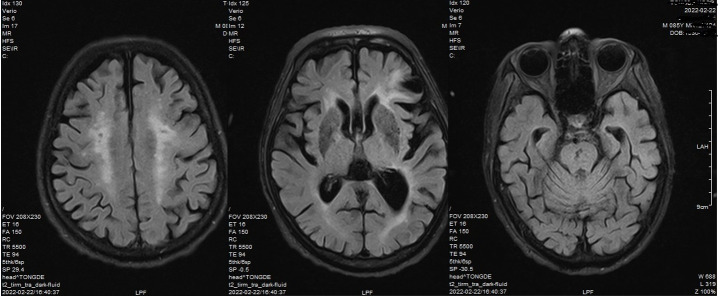

Case report: An 85-year-old man was admitted to the hospital with weakness and slow movement. Shortly after hospitalization, he experienced incomplete small bowel obstruction; thus, parenteral nutrition and intravenous esomeprazole were administered. When intestinal obstruction was relieved, the patient suddenly experienced seizure-like symptoms three times, and 24-h electroencephalogram did not capture any epileptiform pattern. After excluding other causes, we considered serum magnesium deficiency as a diagnosis. Low serum magnesium levels were related to a shortage of absorption due to small bowel obstruction, excess excretion of renal dysfunction, and the use of proton pump inhibitor. However, the exact mechanism underlying the hypomagnesemia-induced seizure-like activity remained unclear. After adjusting the nutritional support and magnesium supplementation, the patient's serum magnesium level returned to normal, and he was free of seizure-like activity.